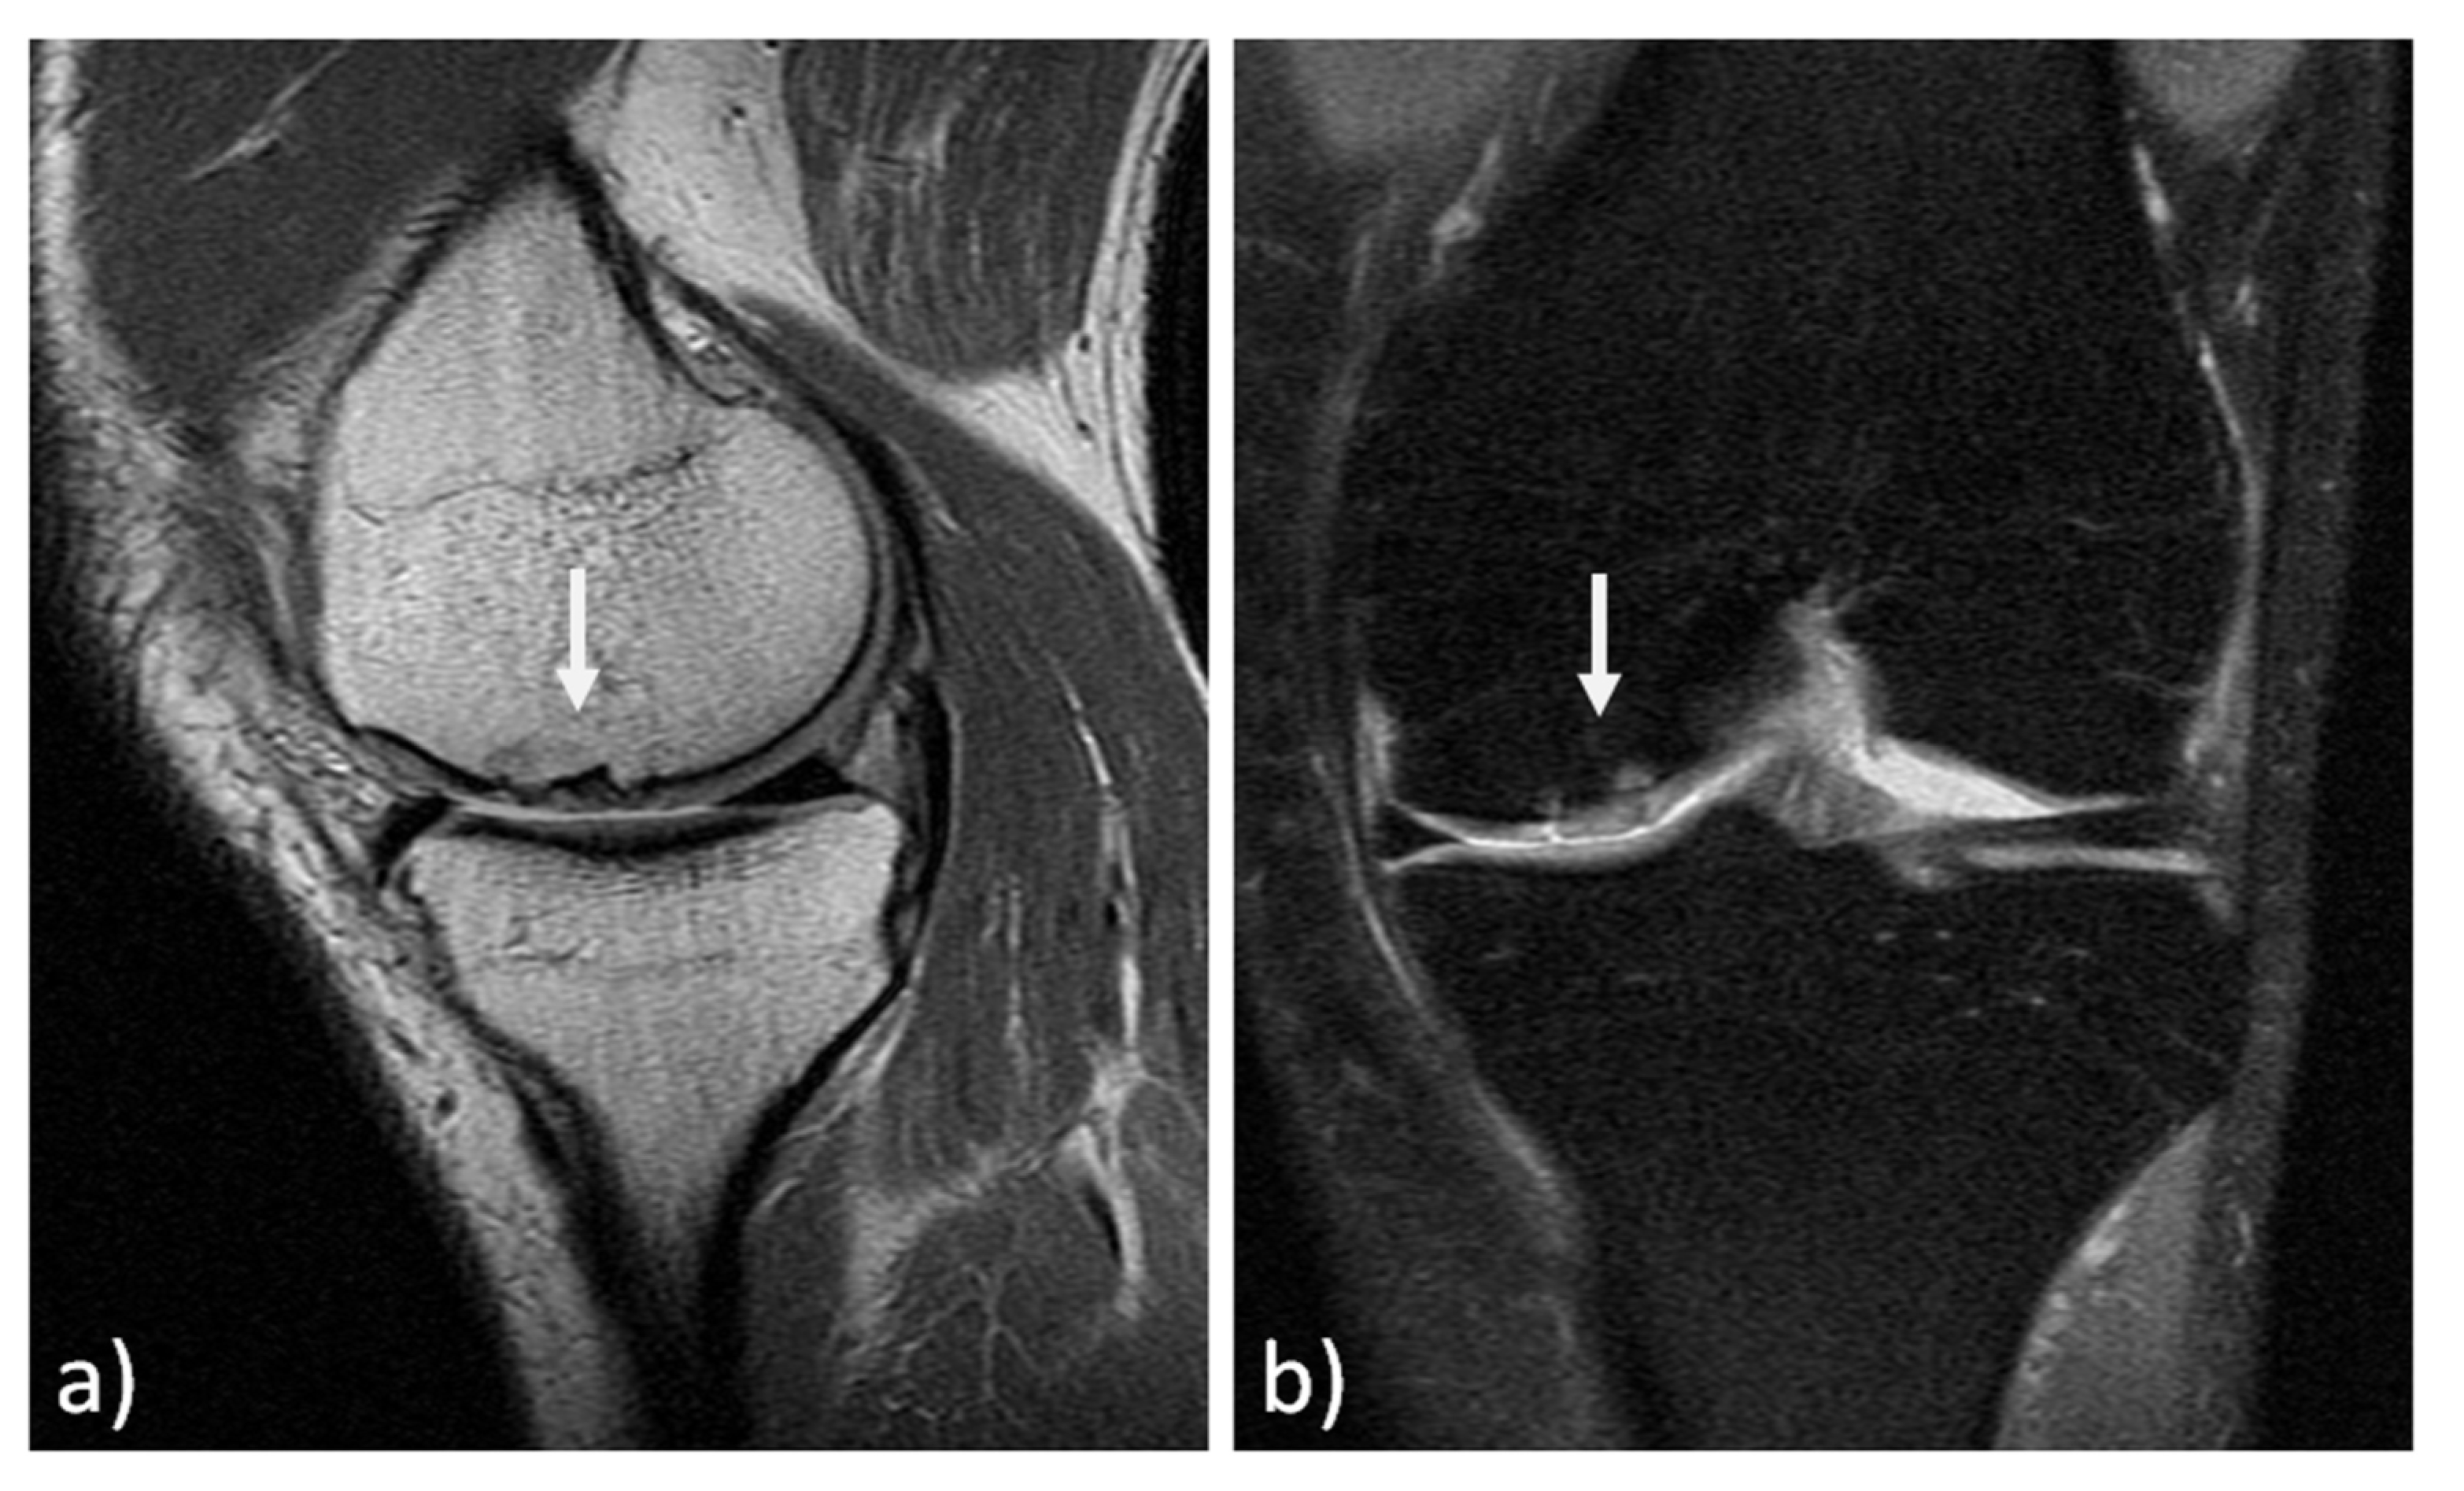

The MRI findings of 30 knees (15 mosaicplasty and 15 MACT), analyzed with the MOCART 2.0 scoring system, showed a high rate of cartilage defect filling in both groups, and a complete integration into the adjacent cartilage in half of the patients in both groups. However, the surface of the repair tissue was damaged in the majority of cases. The structure of the repair tissue was homogeneous in most cases, and the signal intensity was normal (isointense) in half of the patients in both groups. At subchondral bone level, a bony defect or bony overgrowth was reported in the majority of patients, while an edema-like marrow signal was reported in almost half of the patients in both groups (Figure 3 and Figure 4). No significant differences were reported between the two groups in the overall MOCART 2.0 scores and in all the seven subscales (Table 2).

Figure 3. MRI evaluation at 11 years’ follow-up of a medial femoral condyle lesion treated with mosaicplasty in a 37-year-old man. Sagittal 3D "Cube" PD (a) and coronal PD FAT SAT (b) demonstrate a good filling of the defect (arrows) and a complete integration into adjacent cartilage. However, there is an inhomogeneous structure of the repair tissue with adjacent bony overgrowth.